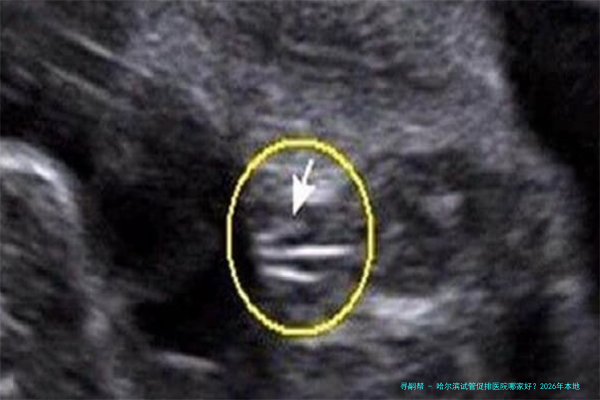

3.卵泡监测:通过B超和水平检测,亲密追踪卵泡发育情况,调节用药。